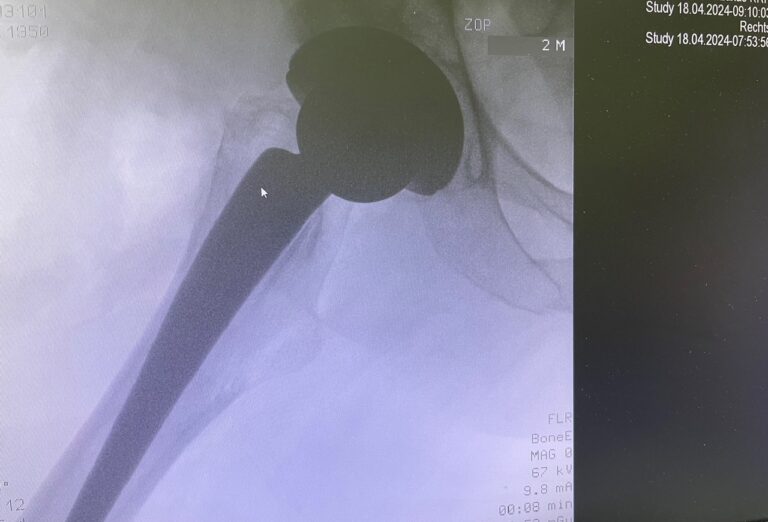

Πώς πραγματοποιείται η επέμβαση

Κατά τη διάρκεια της ολικής αρθροπλαστικής ισχίου:

- αφαιρείται η κατεστραμμένη μηριαία κεφαλή

- τοποθετείται μηριαίο στέλεχος εντός του μηριαίου οστού

- αντικαθίσταται η κοτύλη με τεχνητό κυπέλλιο

- εφαρμόζεται νέα αρθρική επιφάνεια για ομαλή και ανώδυνη κίνηση

Τα εμφυτεύματα είναι κατασκευασμένα από βιοσυμβατά και ανθεκτικά υλικά, όπως τιτάνιο, κεραμικό και ειδικό πολυαιθυλένιο.

Πλεονεκτήματα της τεχνικής AMIS (Πρόσθια Ελάχιστα Επεμβατική Αρθροπλαστική Ισχίου)

Η τεχνική AMIS είναι μια σύγχρονη, ελάχιστα επεμβατική μέθοδος ολικής αρθροπλαστικής ισχίου, που πραγματοποιείται από την πρόσθια προσπέλαση, χωρίς διατομή (τραυματισμό) μυών.